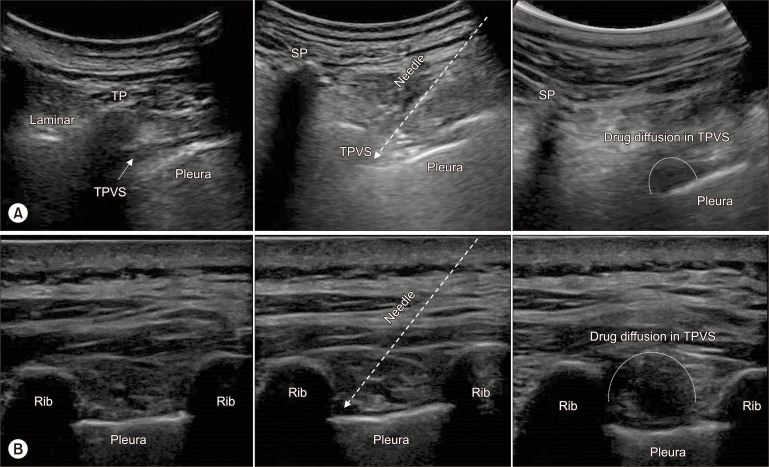

背景:本研究旨在比较肋间神经阻滞(ICNB)和胸椎旁阻滞(TPVB)对急性带状疱疹相关疼痛(ZAP)的治疗效果,以及对带状疱疹后遗神经痛(PHN)的预防效果:本研究共纳入 128 名带状疱疹相关性疼痛患者。他们的病历被分为标准抗病毒治疗(AVT)加 US 引导的 TPVB(TPVB 组)、AVT 加 US 引导的 ICNB(ICNB 组)或单用 AVT(对照组)。手术后 30 天内与带状疱疹(HZ)相关的疾病负担(HZ-BOI)被定义为主要终点,由疼痛严重程度和随访时间综合决定。此外,还记录了手术时间、抢救性镇痛药需求、PHN发生率、与健康相关的生活质量和副作用:结果:与对照组相比,TPVB 组和 ICNB 组的 HZ-BOI-AUC30 明显较低,平均差异分别为 57.5(P < 0.001)和 40.3(P = 0.003)。但是,TPVB 组和 ICNB 组之间没有差异(P = 0.978)。与对照组 AVT 相比,TPVB 组和 ICNB 组在 PHN 发生率、EQ-5D-3L 评分和随访期间的镇痛药需求方面都有明显改善。与TPVB相比,ICNB的手术时间更短(16.47 ± 3.39 vs. 11.69 ± 2.58,P < 0.001):与单纯 AVT 相比,US 引导的 TPVB 和 ICNB 对 ZAP 均有效,并可预防 PHN。可以推荐 ICNB 方法作为传统 TPVB 的替代方法,其手术时间和副作用方面的消耗更少。

Methods: This study enrolled 128 patients with ZAP. Their records were stratified into standard antiviral treatment (AVT) plus US-guided TPVB (the TPVB group), AVT plus US-guided ICNB (the ICNB group) or AVT alone (the control group). Herpes zoster (HZ)-related burden of illness (HZ-BOI) within the post-procedural 30 days was defined as the primary endpoint, determined by a composite of pain severity and follow-up duration. Procedure time, rescue analgesic requirement, PHN incidence, health-related quality of life and side effects were also recorded.